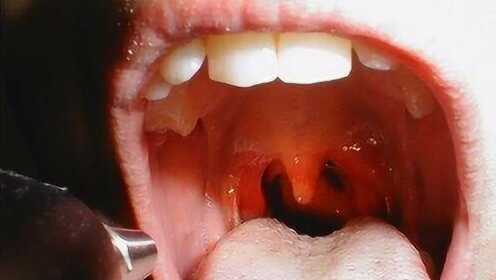

慢性咽炎概述

慢性咽炎是一種常見的喉部疾病,主要表現為咽部不適、干燥、瘙癢、疼痛等癥狀,由于長期受到刺激或感染,咽部黏膜出現慢性炎癥表現,慢性咽炎雖然不是嚴重疾病,但癥狀反復發作,嚴重影響患者的生活質量。